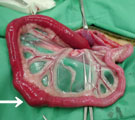

腹部レントゲン。結腸造影も同時施行。小腸領域にX線不透過性異物あり 術中所見。異物により腸閉塞をおこしていた。異物より前の小腸部分は充血 閉塞部分を腸切開し異物を取り出した。小石のようだった。 異物は庭の敷石のような小石で直径2cm位のものだった。

経過:受診時、全身状態はかなり悪化し腹鳴がみられた。CBCおよび血液生化学検査では低張性脱水を示した。腹部レントゲンにて小腸領域に直径2cmほどの角の丸いX線不透過性異物がみられた。この異物は1日経過しても移動がみられないことから小腸内異物による腸閉塞と診断した。ただちに開腹手術となった。小腸を探索し固い異物が腸内に嵌入した閉塞部分を見つけた。閉塞前の小腸部分は充血著明で、小腸粘膜傷害が推測された。閉塞部を切開し異物を取り出した。直径2cm位の庭に敷石のような小石だった。手術翌日より食欲の改善がみられ元気になった。